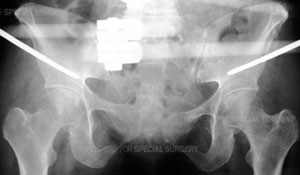

ARadiograph of the pelvis demonstrating application of a pelvic external fixator.

In patients with multiple injuries, treatment begins with the trauma team at the scene, and then subsequently in the emergency room--a team of general surgeons, anesthesiologists and nurses--who work together to control bleeding, address damage to the head and chest, and other organs that may have been affected, such as the bladder and intestines, and to stabilize broken bones. During this early resuscitation phase of treatment, the orthopaedic surgeon may need to stabilize the fracture by using an external frame to temporarily hold the bones in proper alignment while other problems are treated. This is called temporary external fixation. Surgeons construct these frames using steel pins that are inserted into the bone and joined together by clamps and rods and can do so very rapidly.